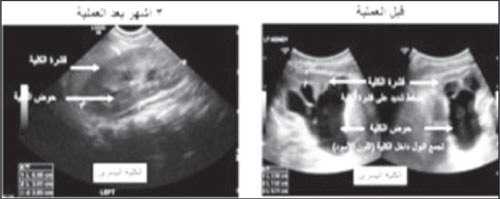

واكتشفت هذه الحالة فترة الحمل حين تبين وجود تضخم في حوض الكلية، وتأكد التشخيص بعد الولادة ومع المتابعة زاد حجم التضخم إلى الدرجة الشديدة وبدأ يؤثر على وظيفة الكلية.

وقد تم إجراء العملية بعمل ثلاث فتحات صغيرة للمنظار الجراحي ومقدارها 5 ملم للكاميرا الجراحية و 3 ملم لإدخال أدوات إجراء العملية، وتكللت ولله الحمد بالنجاح مع سرعة في التعاف، وخرج الطفلان في اليوم التالي بعد العملية.